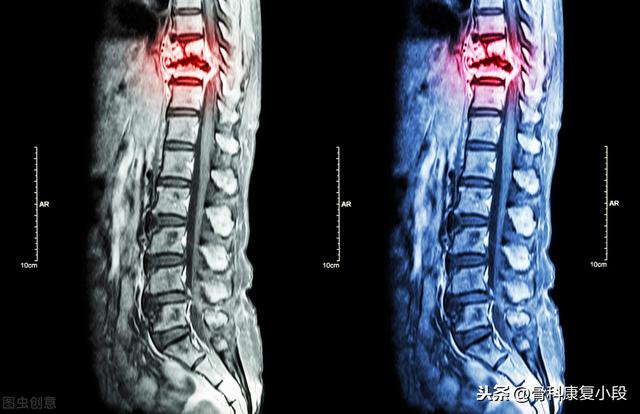

数日前、肺がんの骨転移の患者を診断したばかりで、彼の症状は長期的な腰背部痛で、彼らはいつも腰椎の筋肉の緊張、または腰椎椎間板ヘルニアに苦しんでいると思ったが、気にしなかった、本当に痛みが深刻で、下肢の神経症状が現れ、唯一の検査のために病院へ、そのCT検査に与えられた、明らかな椎骨破壊があることがわかった。......病歴を詳しく調べると、患者は長期的に咳の症状があるため、肺がんの骨転移が強く疑われ、肺のCT検査を行ったところ、主な焦点は......巨大な肺がんであることがわかった。

がんによる骨転移患者の痛みには一定の特徴がありますが、一般的な病気と干渉する症状も見受けられます。もし患者が発生した場合、脊椎の骨転移が神経を刺激し、医師や患者が椎間板ヘルニアによって誘発された症状を誤診しやすく、この時、患者として、体に異常があるため、適時に医師の助けを求め、医師として患者とコミュニケーションを図り、比較的質の高い検査を行い、骨転移のリスクを除外しようとする。例えば、高齢者の長期的な腰痛に対しては、レントゲン検査の代わりにMRI検査を行うことをよく勧める。例えば、慢性的な腰痛を持つ高齢者に対しては、レントゲン検査の代わりにMRI(磁気共鳴画像装置)検査を受けるよう勧めることがよくあります。

胸椎に発生した骨転移性癌を示す。

Dr.シャドウです。骨転移とは、がんが進行した状態のことで、がん細胞が血流にのって骨に転移し、骨に定着・増殖することで、溶骨性骨破壊や骨芽細胞性骨密度増加を引き起こします。腰痛や下肢痛のために進行した肺がんが発見されるがん患者が多いのは残念なことです。

46歳の男性が、腰の持続的な痛みのために受診した症例があった。腰痛は椎間板ヘルニアと考えられた。レントゲンを撮ったが異常は見られなかった。わずかな骨破壊を起こす骨転移はレントゲンでは見えないし、椎間板ヘルニアもレントゲンでは見えない。だから、転移の可能性については特に考えなかった。1週間後、それでも改善が見られないのでCTを撮りに来たところ、腰椎が食べられていた。 このような画像を見て、画像診断医は転移の可能性を考えるに違いないと思い、胸部CT検査をするよう患者に勧めたところ、案の定、肺に腫瘤があり、肺がんの骨転移と考えられ、後日病理検査で確認された。